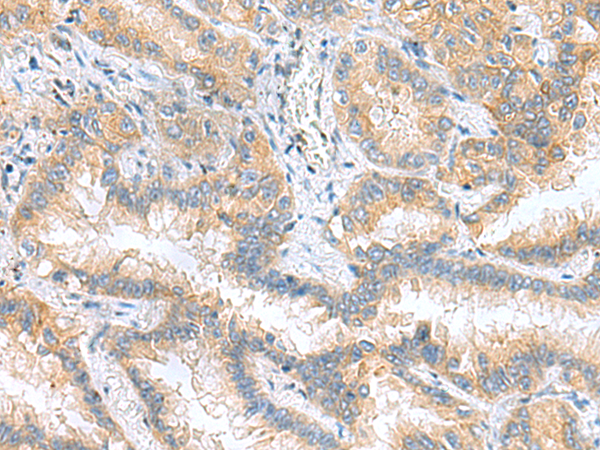

分类: 科研抗体货号: P10251别名: MOM1; PLA2; PLA2B; PLA2L; PLA2S; PLAS1; sPLA2应用: IHC反应种属: Human